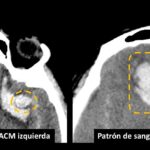

Otra forma de analizar la distribución de la HSA en relación a la ubicación del aneurisma roto, se realizó verificando si había una capa vertical de sangre subaracnoidea de más de 3 mm de espesor o un coágulo de sangre localizado en topografía de cada uno de las siguientes localizaciones, ACI: arteria carótida interna, TIP ACI: bifurcación carotidea, ACM: arteria cerebral media, ACA: Arteria cerebral anterior, ACOMA: arteria comunicante anterior, Vertebro/PICA: segmento V4 de la arteria vertebral, BA: tronco de la arteria basilar, TIP BA: bifurcación de la arteria basilar, ACP: Arteria cerebral posterior.

Fig. 9. Esquema de grosor de la HSA representada en una TC de cerebro sin contraste corte axial, espesor menor a 3 mm (derecha) y espesor mayor a 3 mm (izquierda).

Fig 10. Hemorragia intraparenquimatosa en topografía de la arteria cerebral media izquierda (derecha) y hemorragia intraparenquimatosa en topografía de la arteria comunicante anterior (izquierda).